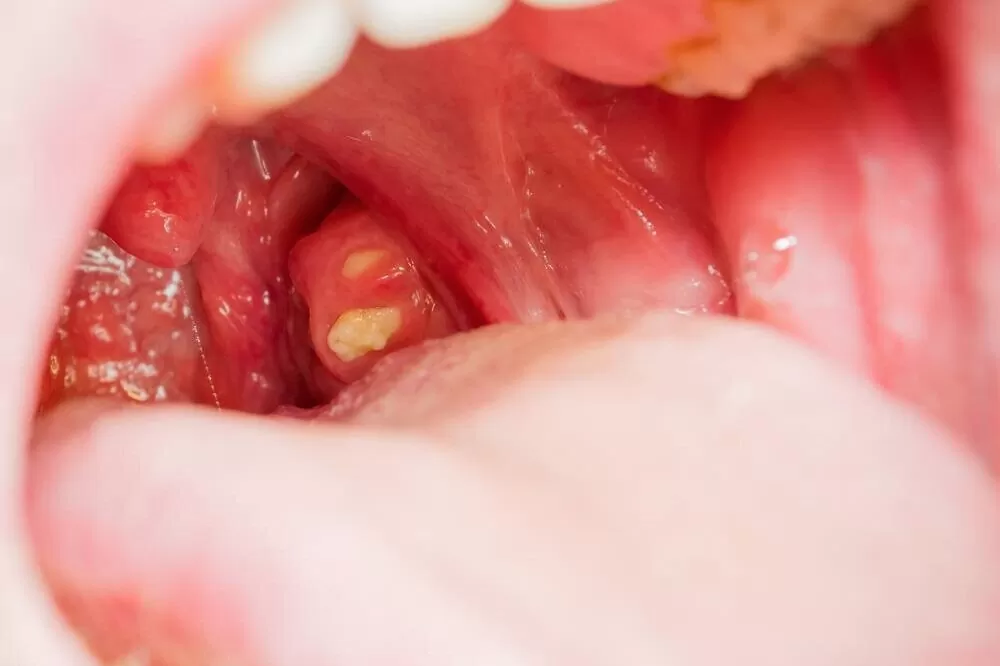

What Tonsil Stones Treatments Mean For Daily Comfort

Look, the bottom line is, in my 15 years working with healthcare providers across the UK, one overlooked factor impacting daily comfort is tonsil stones—those pesky calcified masses that lead to chronic throat irritation and bad breath. What I’ve learned from real-world clinical trials and patient feedback is that effective tonsil stones treatments radically improve […]